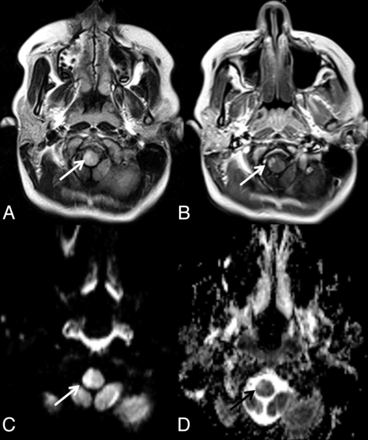

Case 3. Axial T2 FLAIR image shows increased signal in the right medulla oblongata (arrow, A), which demonstrates nonhomogeneous contrast enhancement (arrow, B). Increased signal on DWI (arrow, C) and increased signal on the ADC map consistent with vasogenic edema (black arrow, D) are also noted.